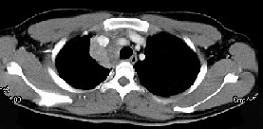

- 单项选择题男,21岁, 干咳,盗汗一月伴消瘦, CT如图,应先考虑为 ( )

A、右上肺结核并纵隔淋巴结核

B、纵隔型肺癌并纵隔淋巴结核转移

C、淋巴瘤

D、右上肺上沟瘤

E、右上肺不张